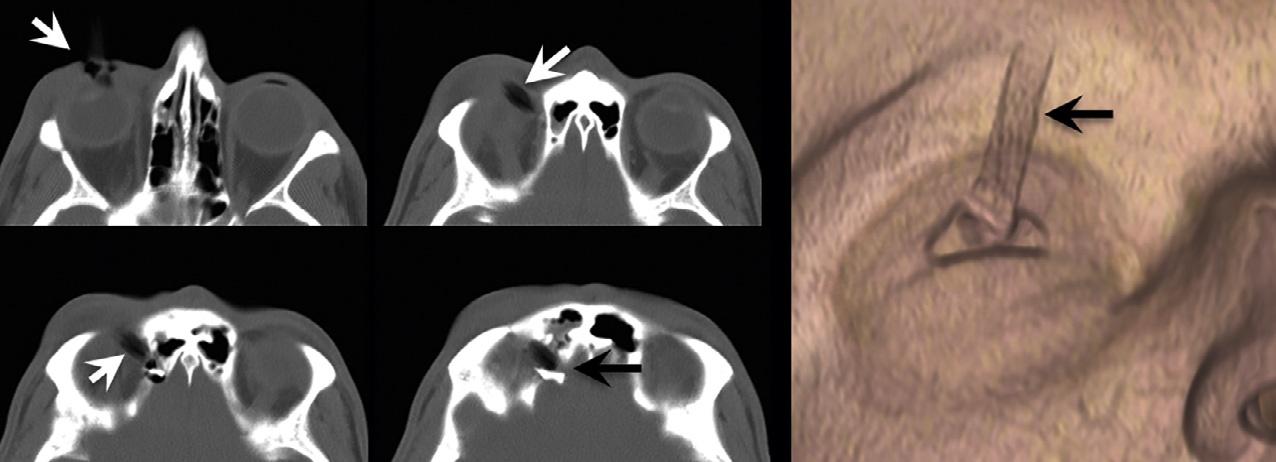

Forexample,atroutineCTX-raybeamenergiesof 120–140kV,theHUvalueofairisapproximately –1000andtheHUvalueofdensecorticalboneisapproximately+1000.Fat,whichfloatsonwater(i.e.,isless dense)istypicallyinthe –30to –70HUrange.Whitematterisabout25HU,graymatterabout35HU,andsoft tissueabout20–30HU.ThestandarddeviationofHU valuesisusuallyinthe 10–20%range.TheHUvalue of invivo bloodis(notsurprisingly)proportionalto thehematocritlevel,andtypicallyabout30.Extravascular,intracranialblood,however,clotsrapidly,andas plasmaisextrudedandresorbedfromtheclot,theconcentrationofthehemoglobinproteincandoubleandtriple,sothatintracranialhemorrhagetypicallymeasures 60–90HU(butrarely >100)(Fig.1.1).Animportant caveatwithregardtoevaluatingtraumapatientsisthat notallpotentialforeignbodiesarehigh-density,highHUstructures.TheCTnumberofadry,woodenforeign body,forexample,istypicallyinthe –100to –170HU range,duetodrywood’sair-filledporousmicrostructure(Yamashitaetal.,2007)(Fig.1.2).

Fig.1.2. Hypodenseforeignbody – awoodenpencil – penetratingthesuperiormedialorbit,withperforationintotheanterior cranialfossa.Notethatthewoodhasasimilarcomputedtomographyappearancetoair.

suchsettings,asubtlecrescenticsubduralhematoma ( 90HU)wouldappearequallyasbrightastheadjacent skull( 1000HU),andhencebeundetectable.Conversely,fat( –30HU)andair( –1000HU)would appearequallydark,andhence,airwithinintraorbital fatresultingfromaparanasalsinusfracturewouldalso beundetectable(Fig.1.3).Byexpandingthewindow widthdisplayandcenteringthegrayscaleatahigher HUlevel,thedifferenceindensitybetweenthesame subduralhematomaandadjacentbonecanbemade visuallyapparent.Similarly,ithasbeensuggestedthat subtlevasogenicedemainacutestrokecanbemoresensitivelydetectedbysoftcopyimagereviewusingnarrowedwindowwidthdisplaysettingsthatexaggerate theHUdifferencesbetweengrayandwhitematter (Levetal.,1999).